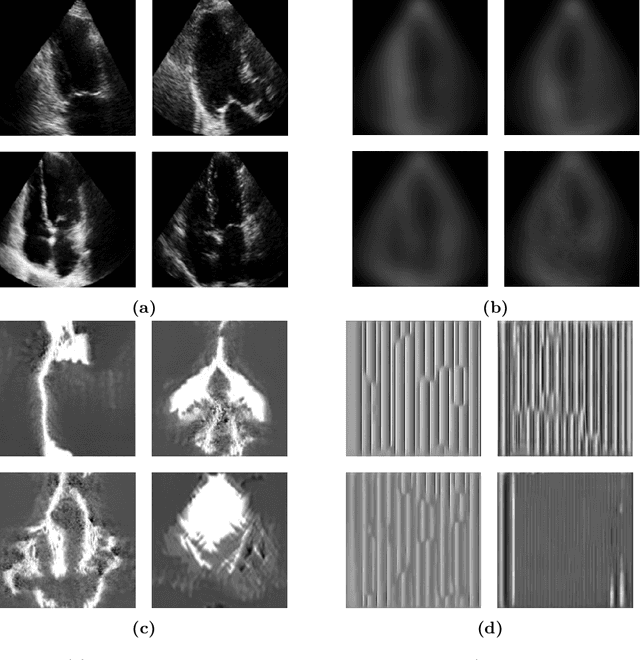

Abstract:Standard deep learning-based classification approaches require collecting all samples from all classes in advance and are trained offline. This paradigm may not be practical in real-world clinical applications, where new classes are incrementally introduced through the addition of new data. Class incremental learning is a strategy allowing learning from such data. However, a major challenge is catastrophic forgetting, i.e., performance degradation on previous classes when adapting a trained model to new data. Prior methodologies to alleviate this challenge save a portion of training data require perpetual storage of such data that may introduce privacy issues. Here, we propose a novel data-free class incremental learning framework that first synthesizes data from the model trained on previous classes to generate a \ours. Subsequently, it updates the model by combining the synthesized data with new class data. Furthermore, we incorporate a cosine normalized Cross-entropy loss to mitigate the adverse effects of the imbalance, a margin loss to increase separation among previous classes and new ones, and an intra-domain contrastive loss to generalize the model trained on the synthesized data to real data. We compare our proposed framework with state-of-the-art methods in class incremental learning, where we demonstrate improvement in accuracy for the classification of 11,062 echocardiography cine series of patients.